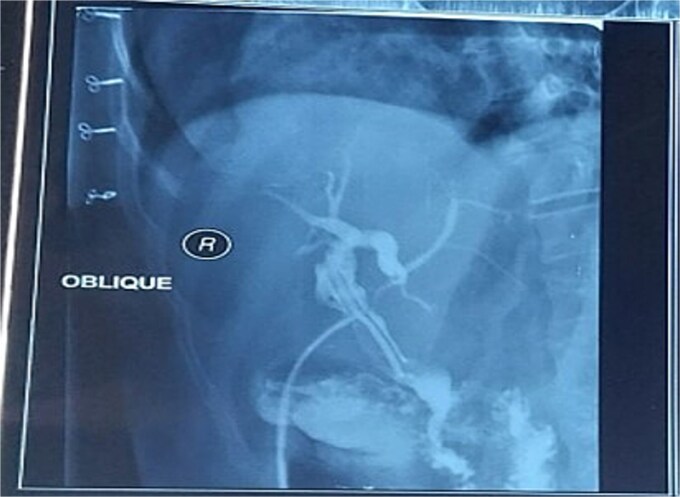

The postoperative course was uneventful, and the patient was discharged on postoperative Day 5. Three weeks later, a T-tube cholangiogram (Fig. 2) confirmed complete stone clearance, after which the T-tube was removed.